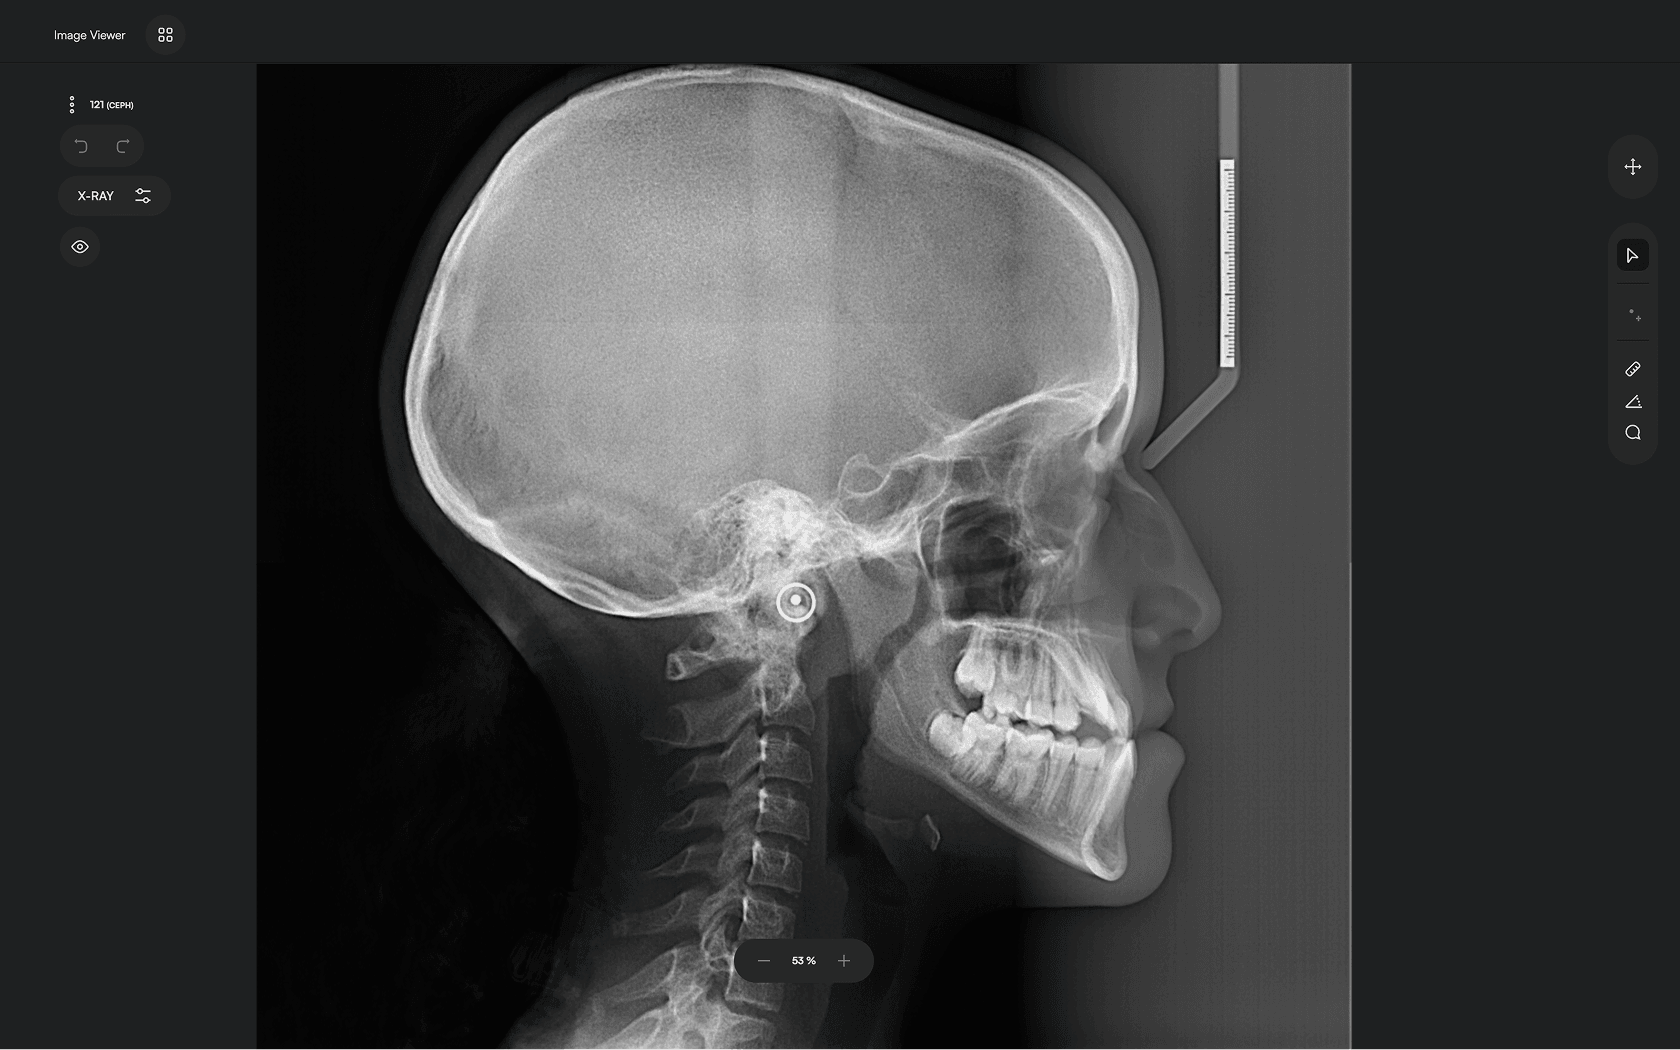

Upload X-ray

Upload your lateral cephalometric X-rays

2